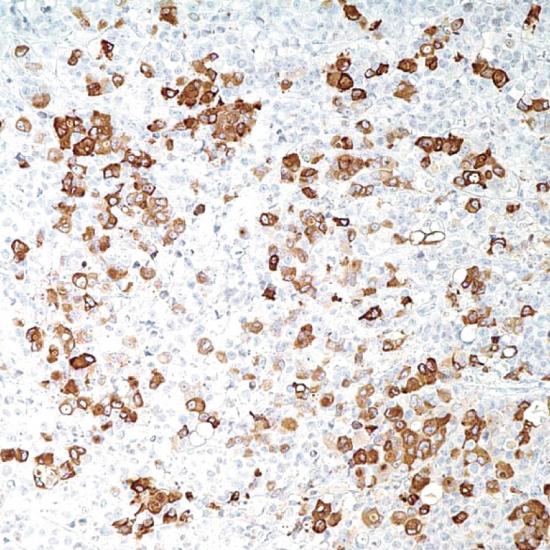

Mammaglobin

乳腺球蛋白是一個(gè)乳腺相關(guān)糖蛋白,它是一個(gè)分泌素家族(包括子宮球蛋白和lipophilin)成員的遠(yuǎn)親。與其他分泌素成員不同,乳腺球蛋白mRNA在乳腺組織中特異表達(dá)。在石蠟組織切片的檢測(cè)中,該抗體檢測(cè)乳腺癌組織中的乳腺球蛋白敏感度高達(dá)80%,如與其他乳腺特異標(biāo)記GCDFP-15聯(lián)合應(yīng)用時(shí),檢測(cè)乳腺癌組織中的乳腺球蛋白敏感度高達(dá)84%。檢測(cè)乳腺球蛋白,在鑒定原發(fā)癌是否發(fā)生轉(zhuǎn)移中起到至關(guān)重要的作用。